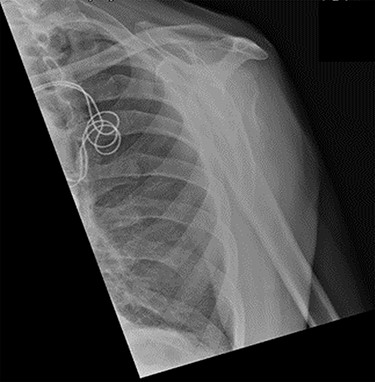

An X-ray of the left shoulder was performed, which revealed acceptable positioning of the fracture. Following a discussion with the patient, a mutual decision was made to manage the injury non-operatively and he was discharged with a collar and cuff sling. Subsequent clinical and radiological review at 1 week and 2 weeks post-injury showed the soft tissues to be healing well and the fracture to be well-positioned (Figs 5 and 6).

Antero-posterior view X-ray taken 1 week post-injury showing acceptable positioning of the fracture.